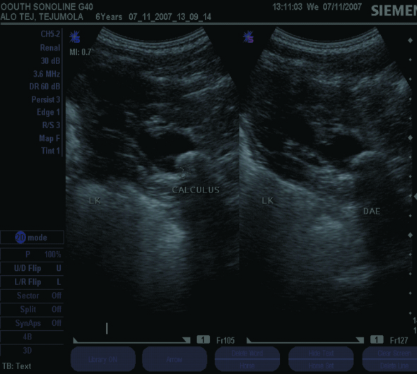

Kidney Stone In A 7-Year Old Girl

Dr. A. A. Olatunji, A. F. Adekanmbi, T. A. Ogunlesi, M. B. Fetuga (Author)

41-44